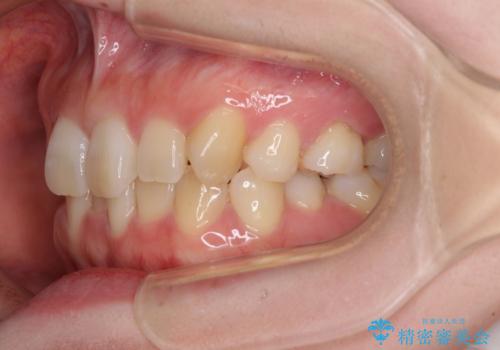

- 前歯のデコボコと強い咬みしめを気にして来院された患者様です。

インビザラインを用いて、前歯の叢生を解消するとともに、ディープバイトを改善していくこととしました。

上顎に乳歯が左右1本ずつ残っていたため、若干咬み合わせに不具合が残りましたが、強い咬合力の原因であったディープバイトをしっかりと改善することができました。